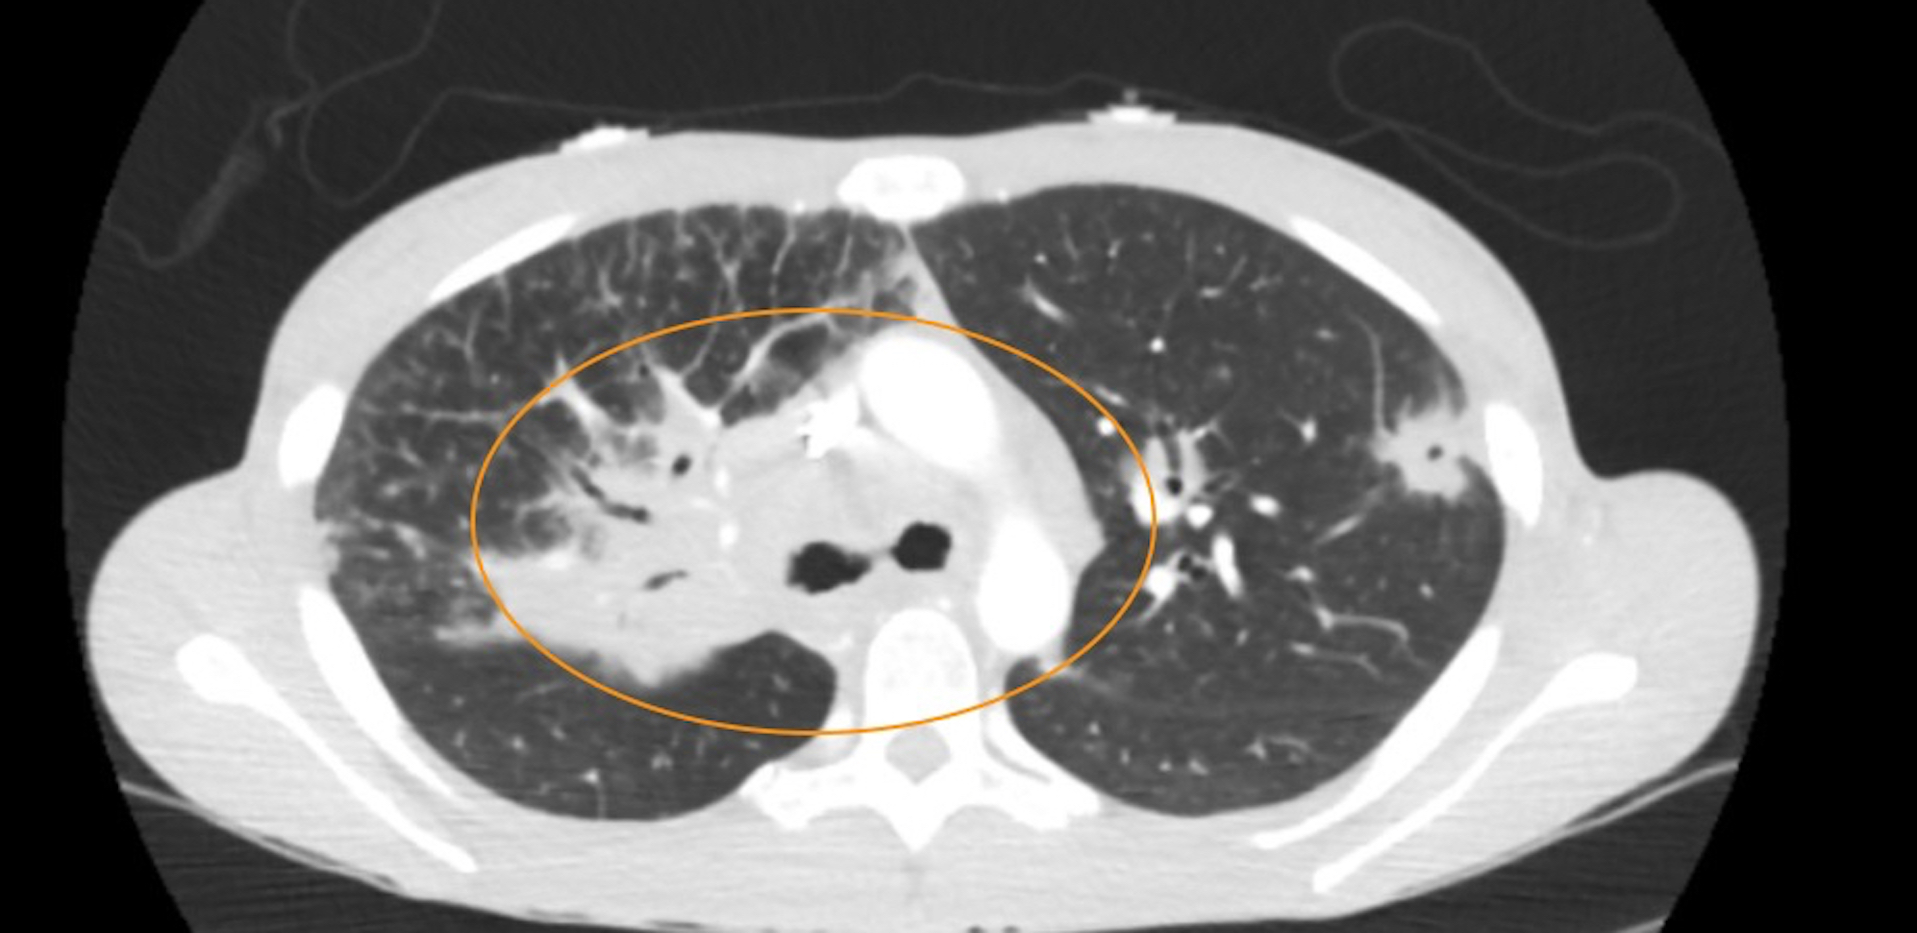

Sarcoidosis is a multisystem inflammatory disease characterized by non-caseating granulomas, primarily affecting the lungs but also involving other organs such as the skin, eyes, and heart.1 Due to its variable presentation, diagnosing sarcoidosis in the emergency department (ED) can be challenging. We report a case of a 28-year-old African American female presenting with acute dyspnea on exertion, significant weight loss, and multiple cutaneous nodules. Her diagnostic workup revealed hypercalcemia, diffuse pulmonary nodules, and extensive lymphadenopathy on imaging. Biopsy of her eyelid lesions confirmed non-caseating granulomas, leading to a diagnosis of sarcoidosis. She was initiated on high-dose steroids and evaluated for further immunologic therapy. Sarcoidosis presents a diagnostic challenge due to its nonspecific symptoms, often mimicking more common conditions.2 Early recognition in the ED is critical to prevent disease progression. This case underscores the importance of considering sarcoidosis in patients with unexplained systemic symptoms and highlights the need for a multidisciplinary approach to management.